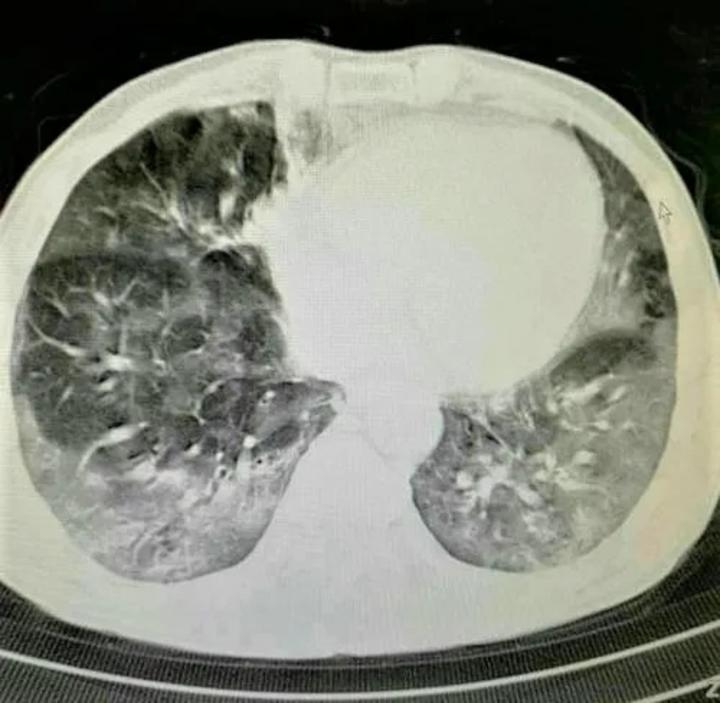

喝百草枯肺部纤维化,百草枯肺部纤维化图片

上消化道刺激腐蚀,肝和(或)肾损害,随后出现肺部损伤,肺组织纤维化

毒素会让肺部纤维化,导致呼吸衰竭,这是百草枯中毒死亡的最主要原因

病例百草枯中毒肺间质纤维化1例ct影像表现

一开始只是肺部水肿,接着肺部就会纤维化,造成人呼吸困难.

百草枯肺部纤维化图片

肺纤维化的ct图片